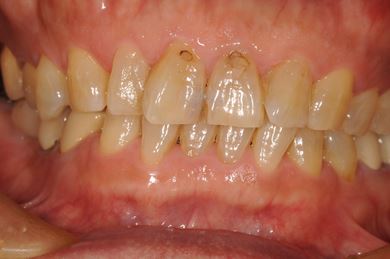

インプラントの症例写真 IMPLANT

インプラント治療+セラミック治療

| 主訴 | 部分入れ歯のバーが舌に当たるため、奥歯2本のインプラント治療を希望。 | ||||||||||||||||||||||||||||||||

| 治療方針 | 右下欠損部分をインプラント治療にて、機能的・審美的回復を行う。 | ||||||||||||||||||||||||||||||||

| 治療内容 | インプラント2本、メタルボンドセラミッククラウン8本、メタルボンドセラミック用土台6本 | ||||||||||||||||||||||||||||||||